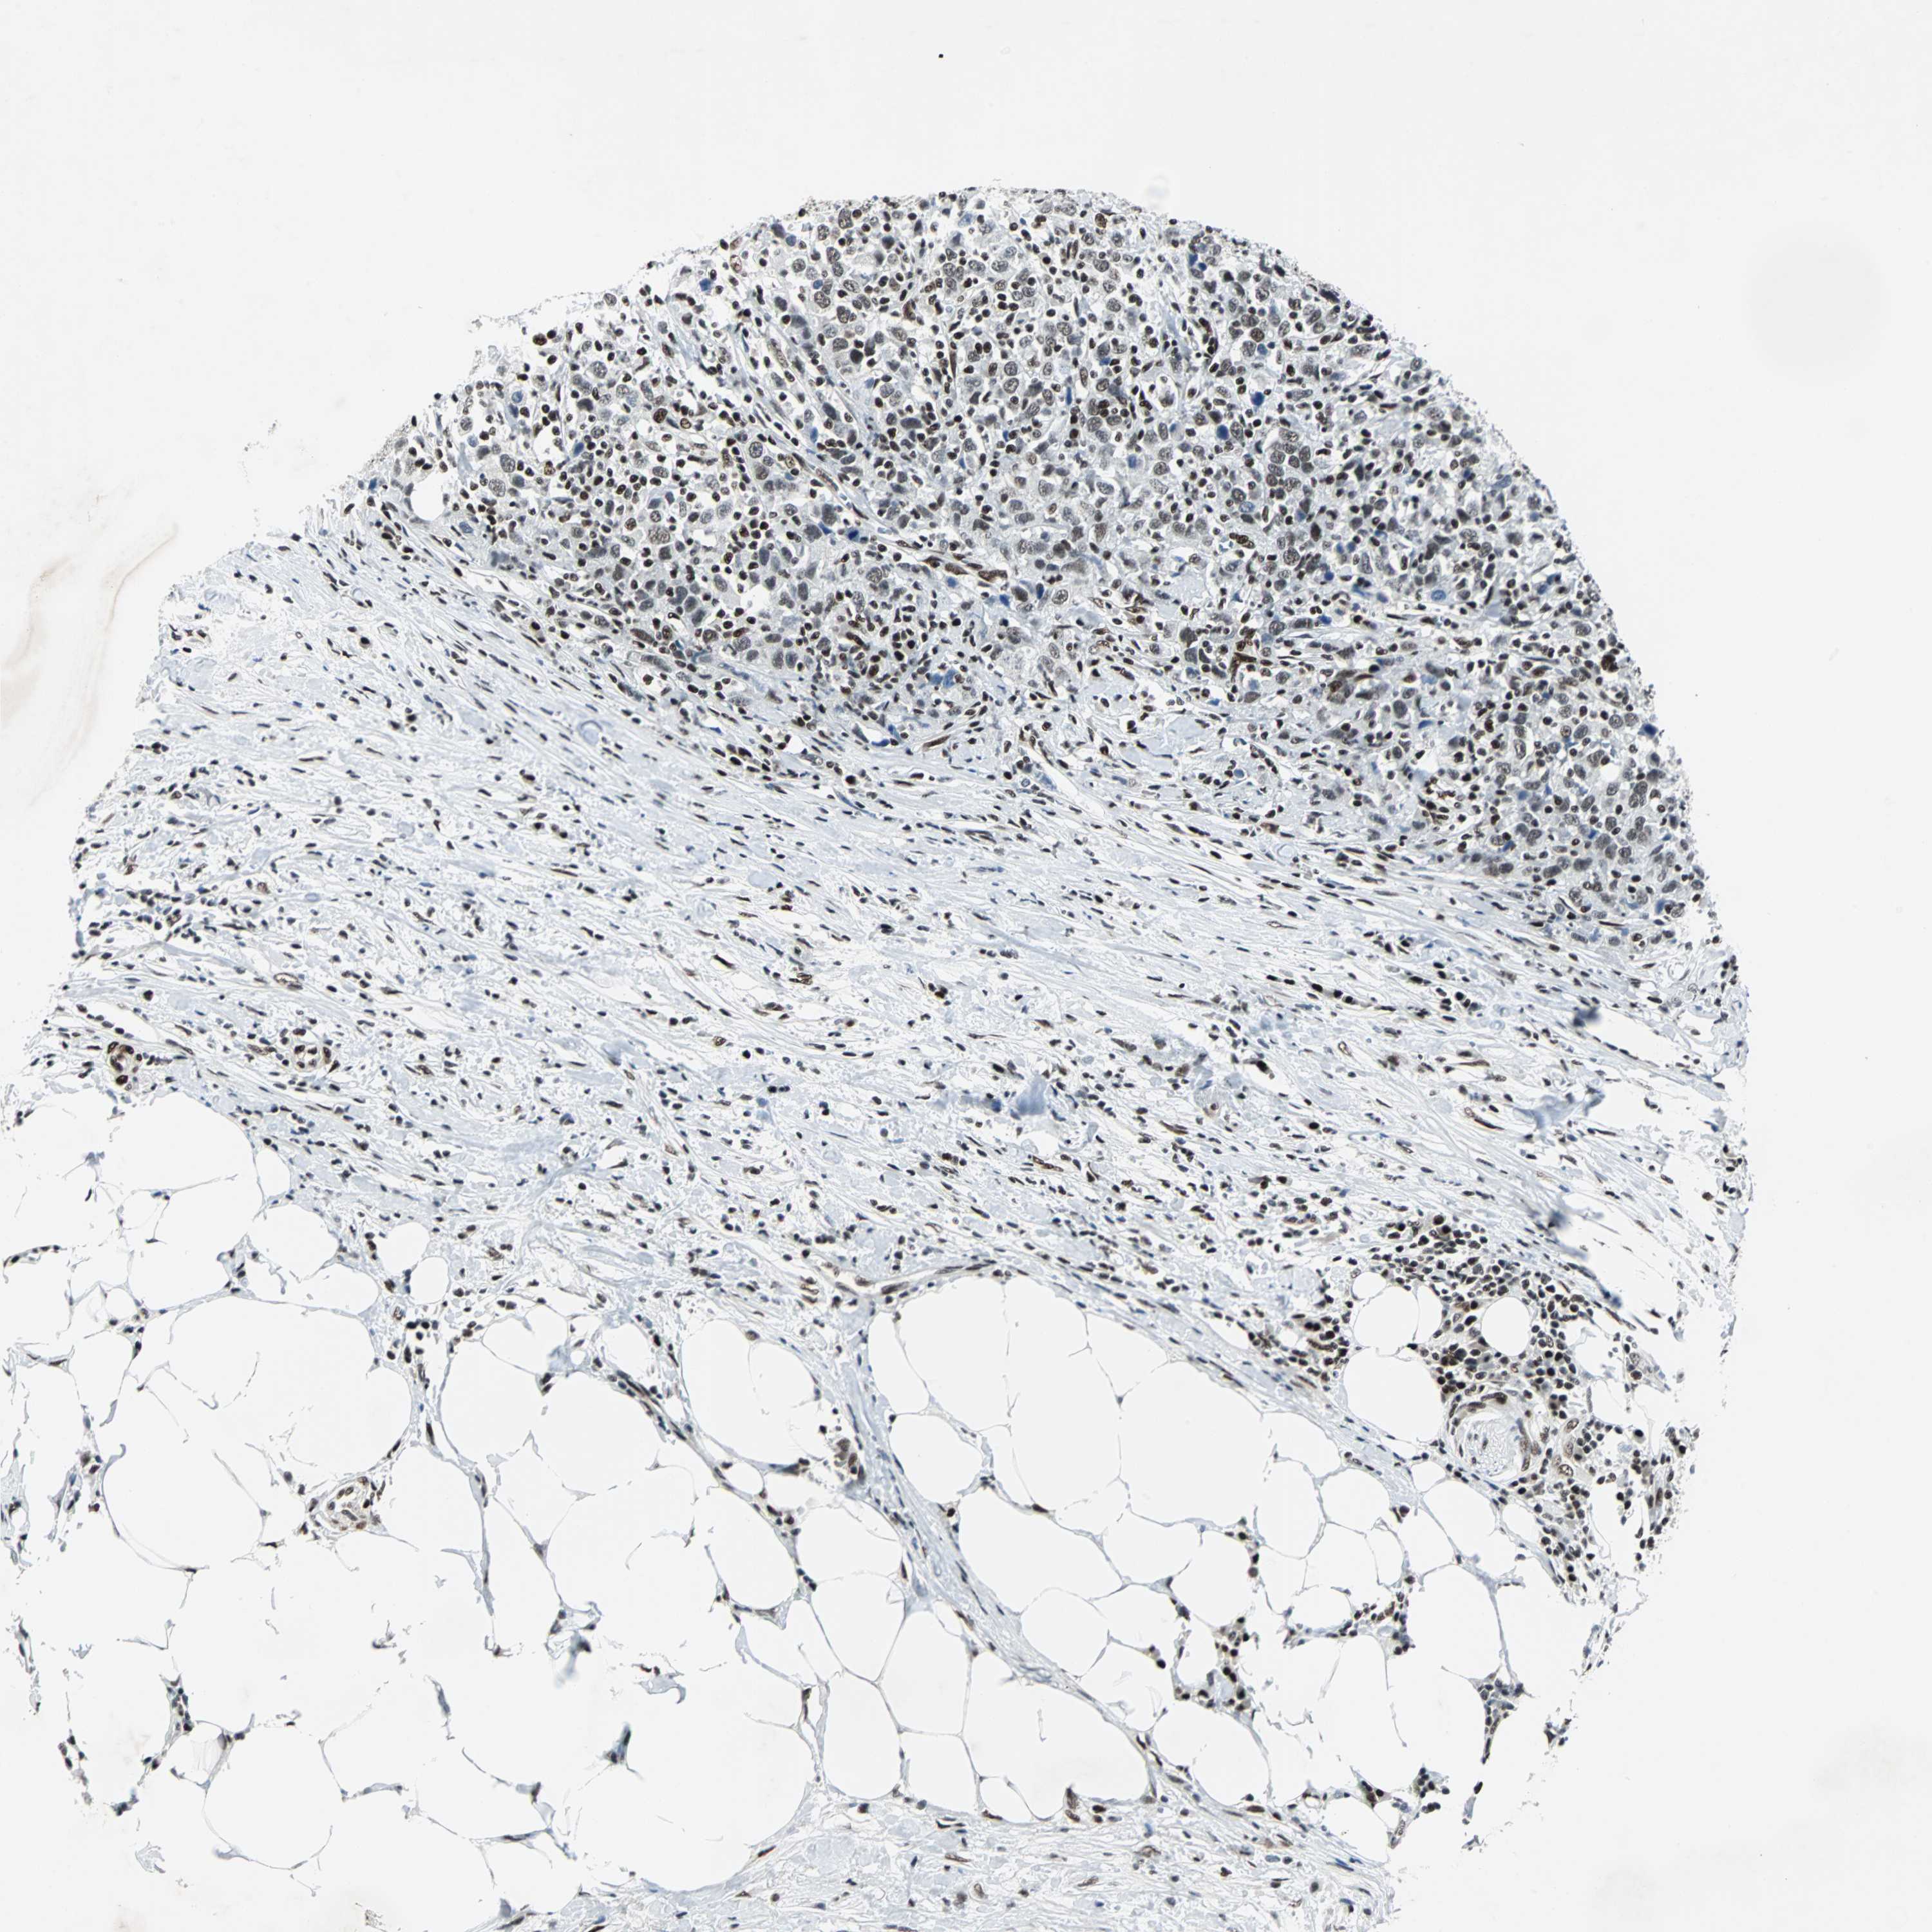

UROTHELIAL CANCER - Protein expressioni

A mouse-over function shows sample information and annotation data. Click on an image to view it in a full screen mode. Samples can be filtered based on level of antibody staining by selecting one or several of the following categories: high, medium, low and not detected. The assay and annotation is described here.

Note that samples used for immunohistochemistry by the Human Protein Atlas do not correspond to samples in the TCGA dataset.

Antibody stainingi

Antibody staining in the annotated cell types in the current human tissue is reported as not detected, low, medium, or high, based on conventional immunohistochemistry profiling in selected tissues. This score is based on the combination of the staining intensity and fraction of stained cells.

Each image is clickable and will lead to virtual microscopy that enables deeper exploration of all samples and also displays staining intensity scores, fraction scores and subcellular localization as well as patient and tissue information for each sample.

Antibody HPA004807

Antibody HPA007114

Staining

High

Medium

Low

Not detected

Intensity

Strong

Moderate

Weak

Negative

Quantity

>75%

75%-25%

<25%

None

Location

Nuclear

Cytoplasmic/membranous

Cytoplasmic/membranous,nuclear

Urothelial carcinoma, High grade

Urothelial carcinoma, Low grade